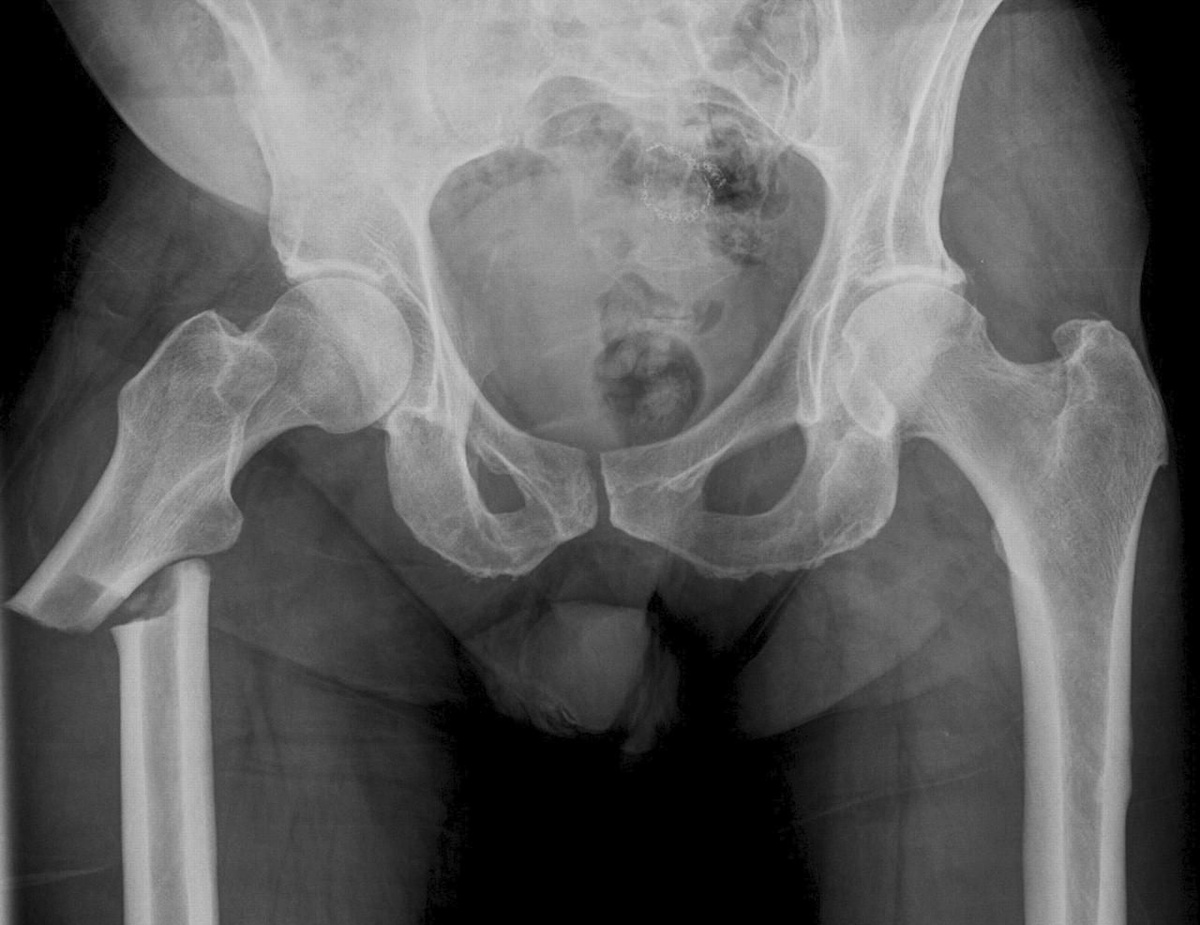

• Боль над лобковой костью – может возникнуть в результате травмы одной из ветвей лобковой кости при переломах таза или же может ошибочно расцениваться, как боль в костях, однако будет связана с заболеваниями органов малого таза.

• Боль в бедренной кости может быть связана с травматическим повреждением в результате остеопороза, или сильного удара в область повреждённой нижней конечности. Боль в бедре также может возникнуть из-за онкологического процесса.